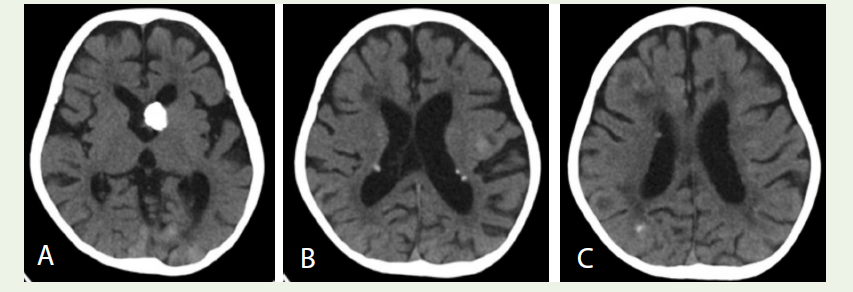

Case 4: A 3-year-old girl with developmental delay had multiple calcified cortical tubers and subependymal nodules on CT, including a mass at the foramen of Monro (Figure 4A–C), consistent with tuberous sclerosis.

control and ophthalmologic assessment [13].Case 4: Tuberous Sclerosis:

Clinical presentation: A 3-year-old girl with global

developmental delay began having generalized seizures at 6 months

of age. There were no focal neurological deficits or noted skin lesions

on examination.Imaging findings: Cranial CT revealed multiple typical TSC

abnormalities. A calcified mass was noted at the le foramen of Monro,

extending into the le lateral ventricle and causing mild dilation of

the le ventricle [Figure 4A]. Many calcified subependymal nodules

lined the walls of both lateral ventricles

[Figure 4B]. The cerebral

cortex contained numerous tubers seen as mixed-density lesions in

the bilateral frontal and parietal lobes, with scattered calcifications

[Figure 4C]. Adjacent white matter showed areas of low attenuation.

These findings are classic for tuberous sclerosis complex (TSC).

Diagnosis: The imaging findings of multiple cortical tubers

and calcified subependymal nodules (including a large lesion at

the foramen of Monro) confirm the diagnosis of TSC, likely with a

subependymal giant cell astrocytoma.

Figure 4: A: Axial CT image showing a calci昀椀ed mass at the left foramen of Monro extending into the left lateral ventricle causing mild ventricular dilation. B: Axial CT image showing multiple calci昀椀ed subependymal nodules along the walls of both lateral ventricles. C: Axial CT image showing multiple cortical tubers in the bilateral frontal and parietal lobes, with scattered calci昀椀cations and adjacent white matter changes